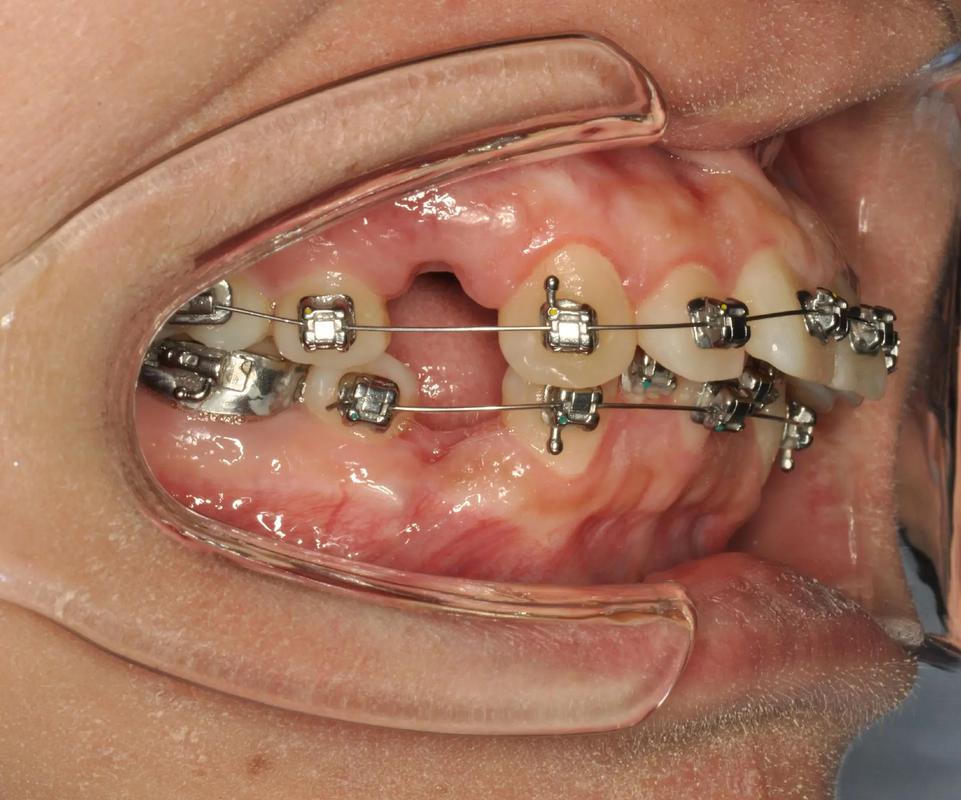

边缘粗糙或位置不当:

(图片来源网络,侵删)- 带环在制作或粘接过程中,如果边缘打磨不光滑,存在毛刺、锐边或不规则处,就会像小刀子一样不断摩擦娇嫩的口腔黏膜。

- 带环的位置如果略微偏离理想位置,或者牙齿在移动过程中改变了位置,都可能使带环边缘更贴近甚至压迫黏膜。

带环内部结构刺激:

带环内部通常焊接有颊面管(用于固定弓丝)或舌侧附件,这些附件的边缘如果处理不当,也可能刺激到对应位置的黏膜(如颊黏膜、舌侧)。